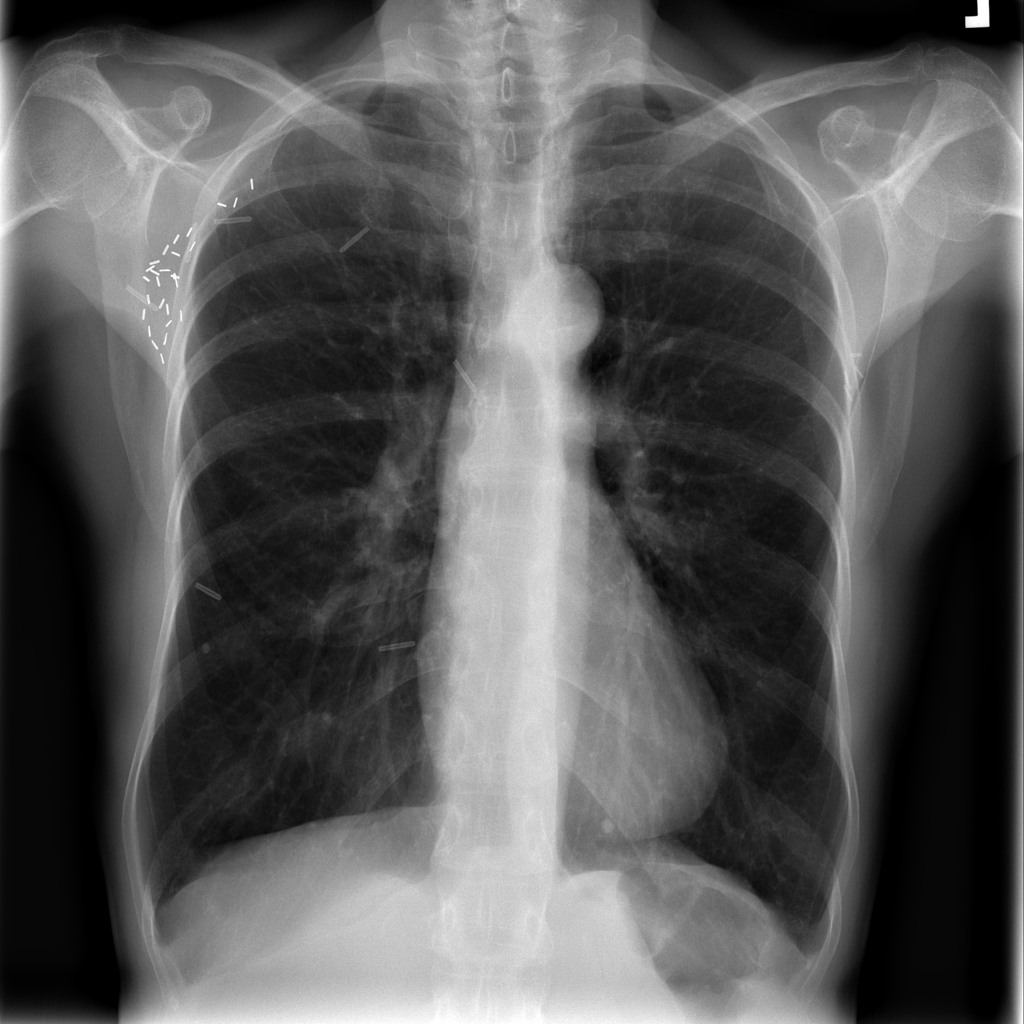

PAT-C255 · IMG-000Emphysema

PAT-C255 · IMG-000

PA